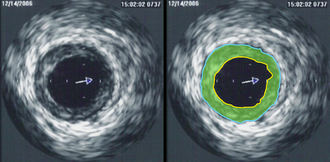

Ehokardiografija je skupina neinvazivnih pretraga srca ultrazvukom. Temelji se na registraciji ultrazvučnih valova što ih reflektiraju srčane strukture. Ehokardiografija je dominantna metoda kardiološkog pregleda koja, pouzdanim podatcima, najčešće otklanja potrebu za invazivnim pretragama srca. Daje ključne podatke za dijagnozu: funkcijske parametre, točne mjere srčanih šupljina i debljine stijenki, oblik srčanih struktura, vrijednosti intrakardijalnih tlakova, procjenu težine bolesti srčanih zalistaka i drugo. Jednodimenzijska ehokardiografija (M-prikaz, od eng. motion: kretanje) prikazuje gibanje srčanih struktura s pomoću jednoga piezoelektričnoga kristala i daje najbolji vremenski prikaz zbivanja u srcu. Dvodimenzijska ehokardiografija daje slojevne slike srčanih struktura u "živoj slici" s dobrom prostornom orijentacijom. Dopplerova ehokardiografija primjenjuje se osobito u dijagnostici prirođenih i stečenih bolesti srca. [2]